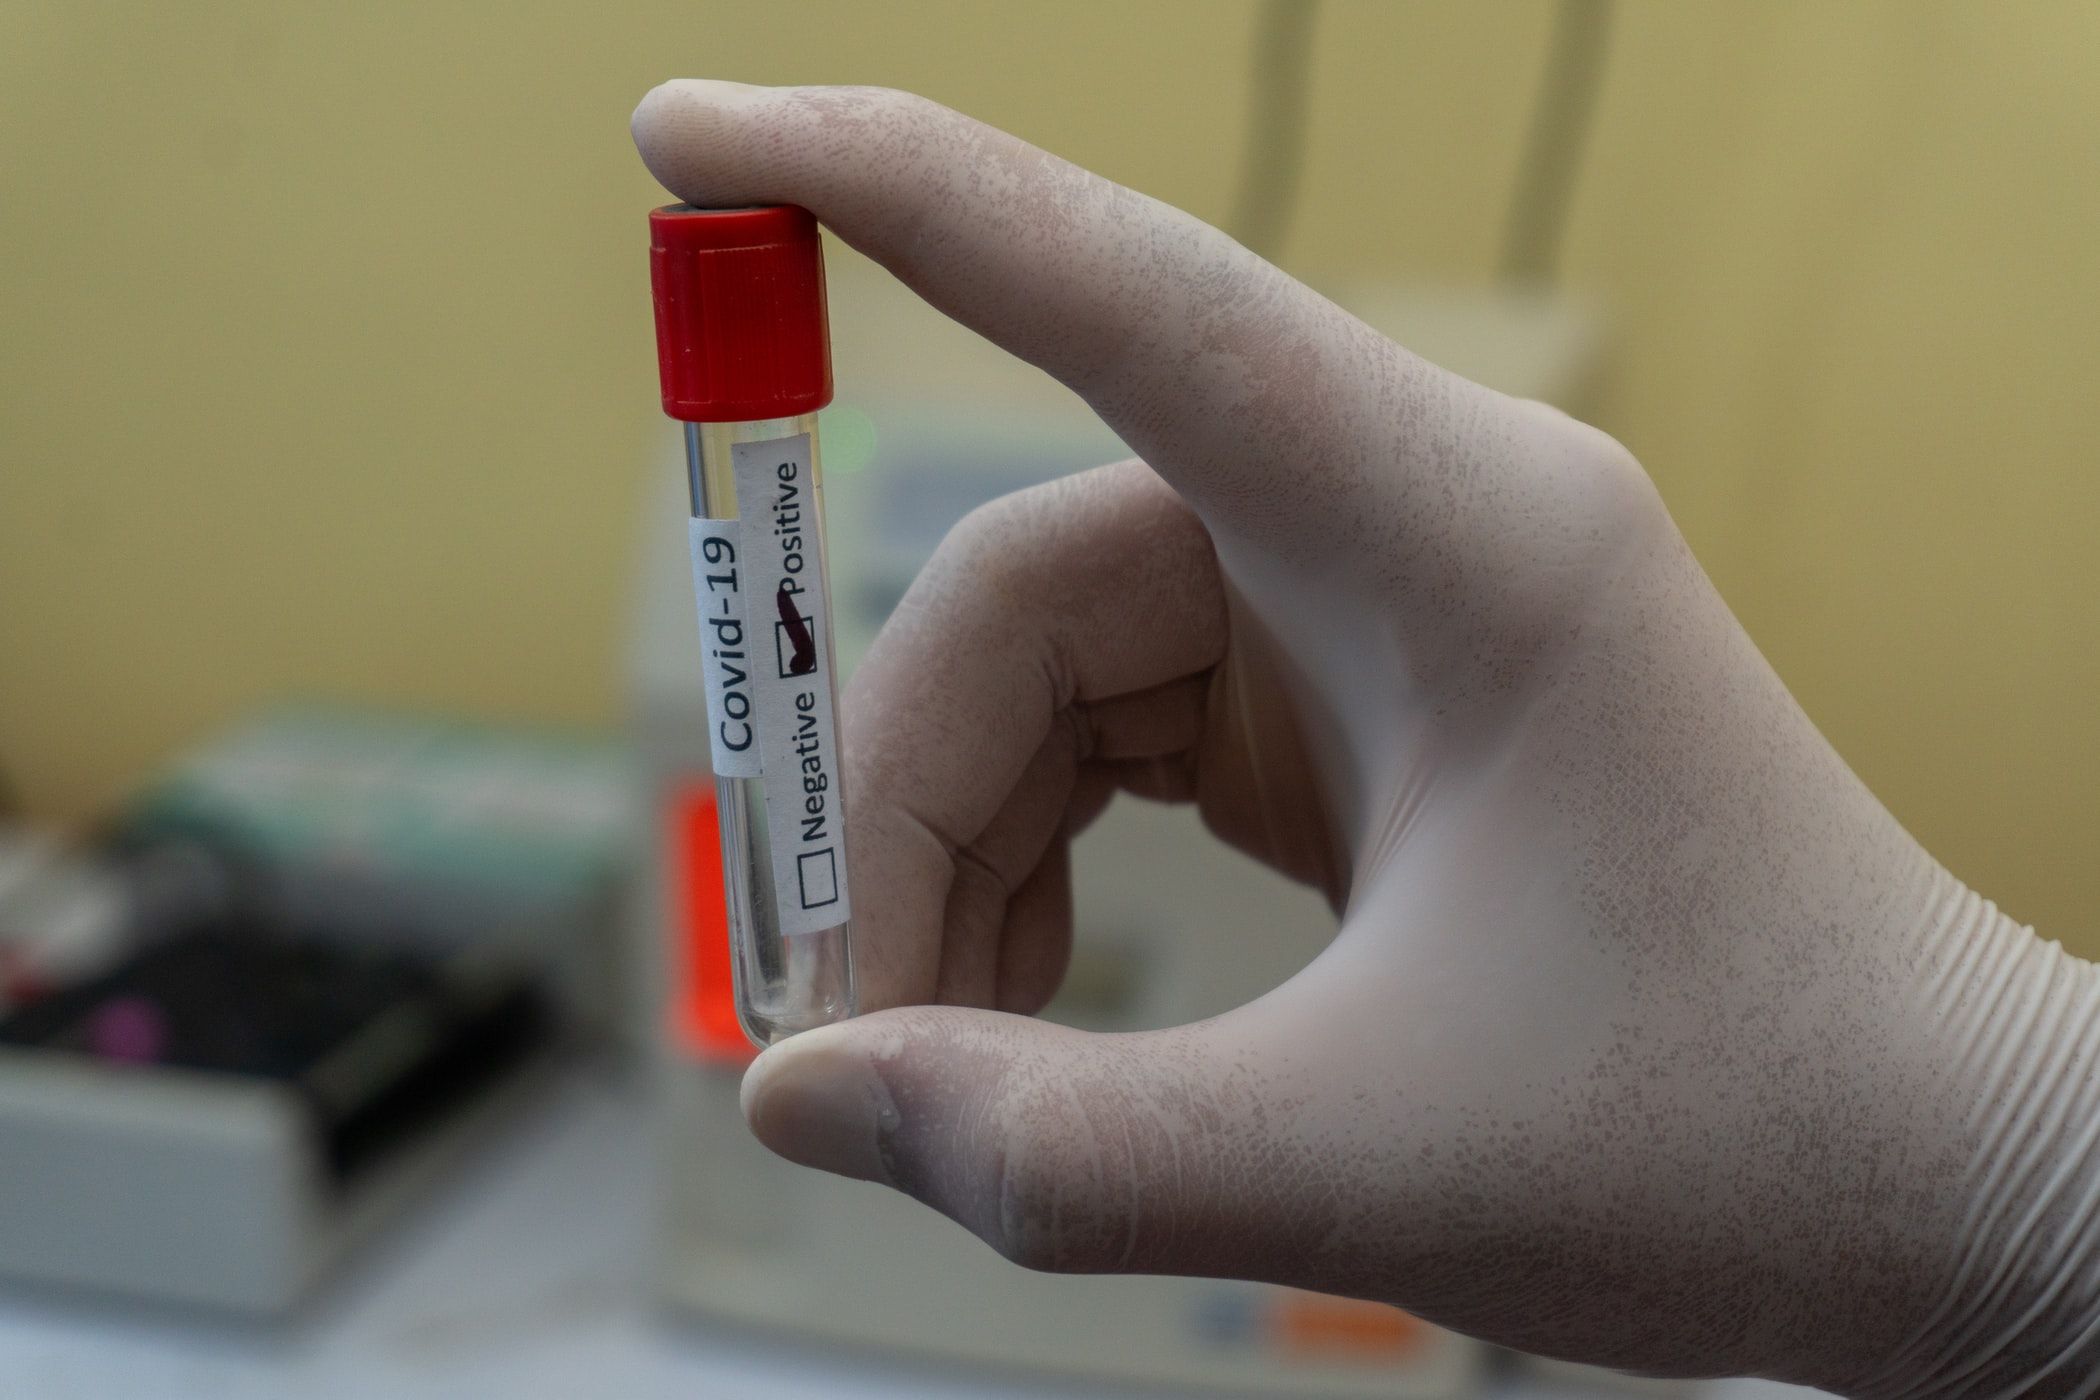

The entire world is engulfed into a corona pandemic attack. At present, there are 191127 positive cases of noble COVID-19 infection all over the world with total fatalities of 7807 according to a report by the World Health Organization(WHO).

The entire world is engulfed into a corona pandemic attack. At present, there are 191127 positive cases of noble COVID-19 infection all over the world with total fatalities of 7807 according to a report by the World Health Organization(WHO).